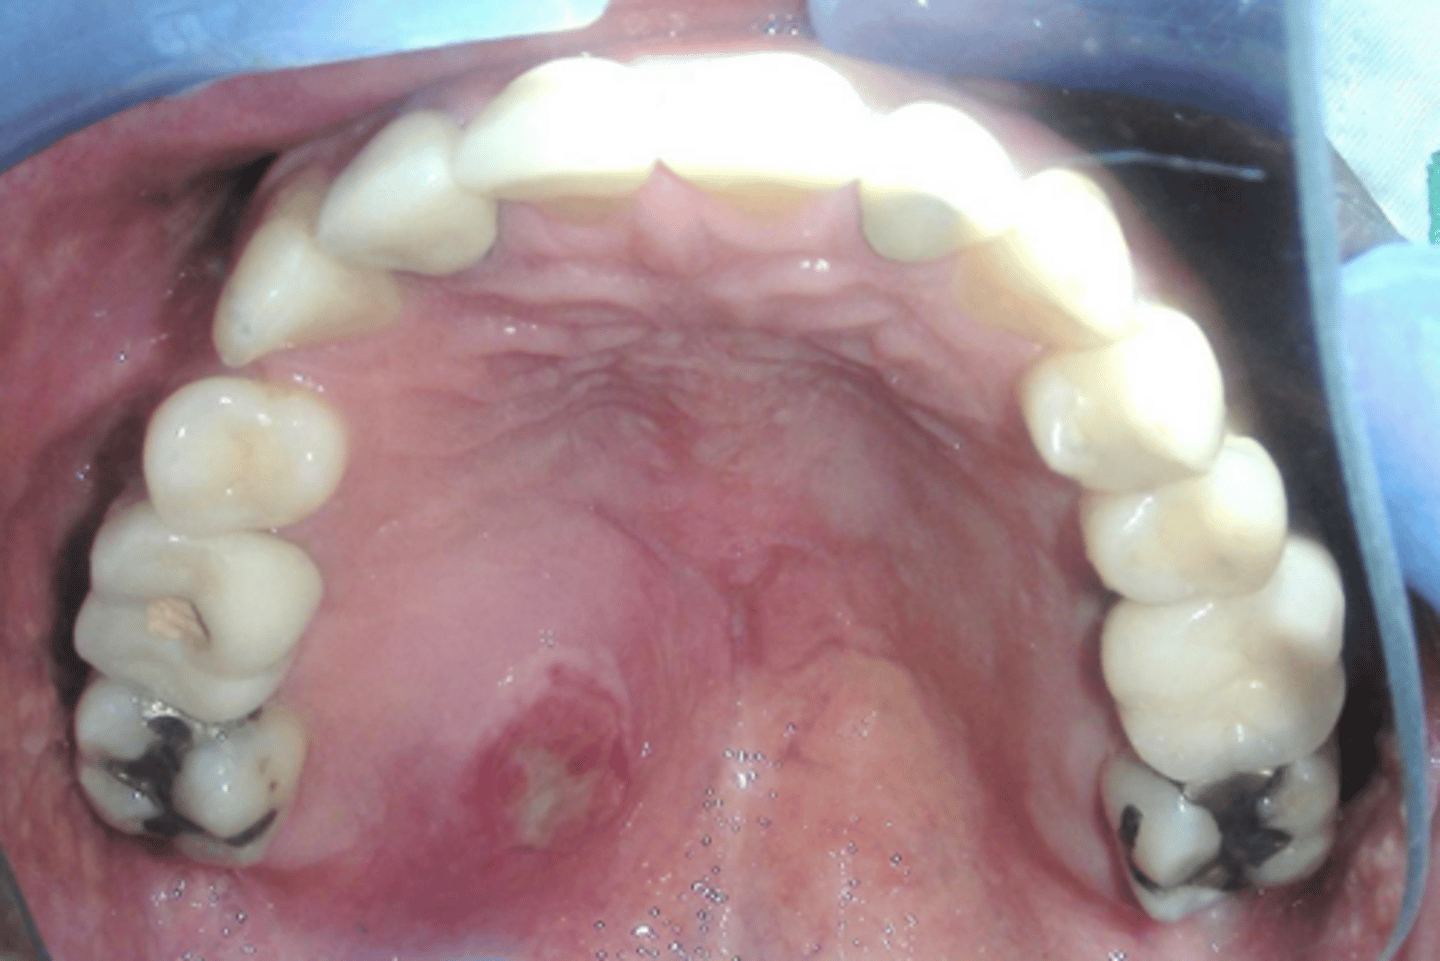

- Xerostomia

- Dysphagia

- Cervical caries

- Fissured tongue with atrophy of papillae

- Secondary candidiasis

5 oral symptoms of Sjögren Syndrome

Sjögren Syndrome

Patient presents to your office complaining of xerostomia and dysphagia. Patient admits that they also experience dry eyes. Patient also has numerous cervical caries, fissured tongue with atrophy of papillae, and a minor case of secondary candidiasis. Upon physical examination, you notice bilateral swelling of the parotid glands. Lab work up shows elevated IgG, positive rheumatoid factor (RF) and Antinuclear antibodies (ANA). What is the diagnosis?